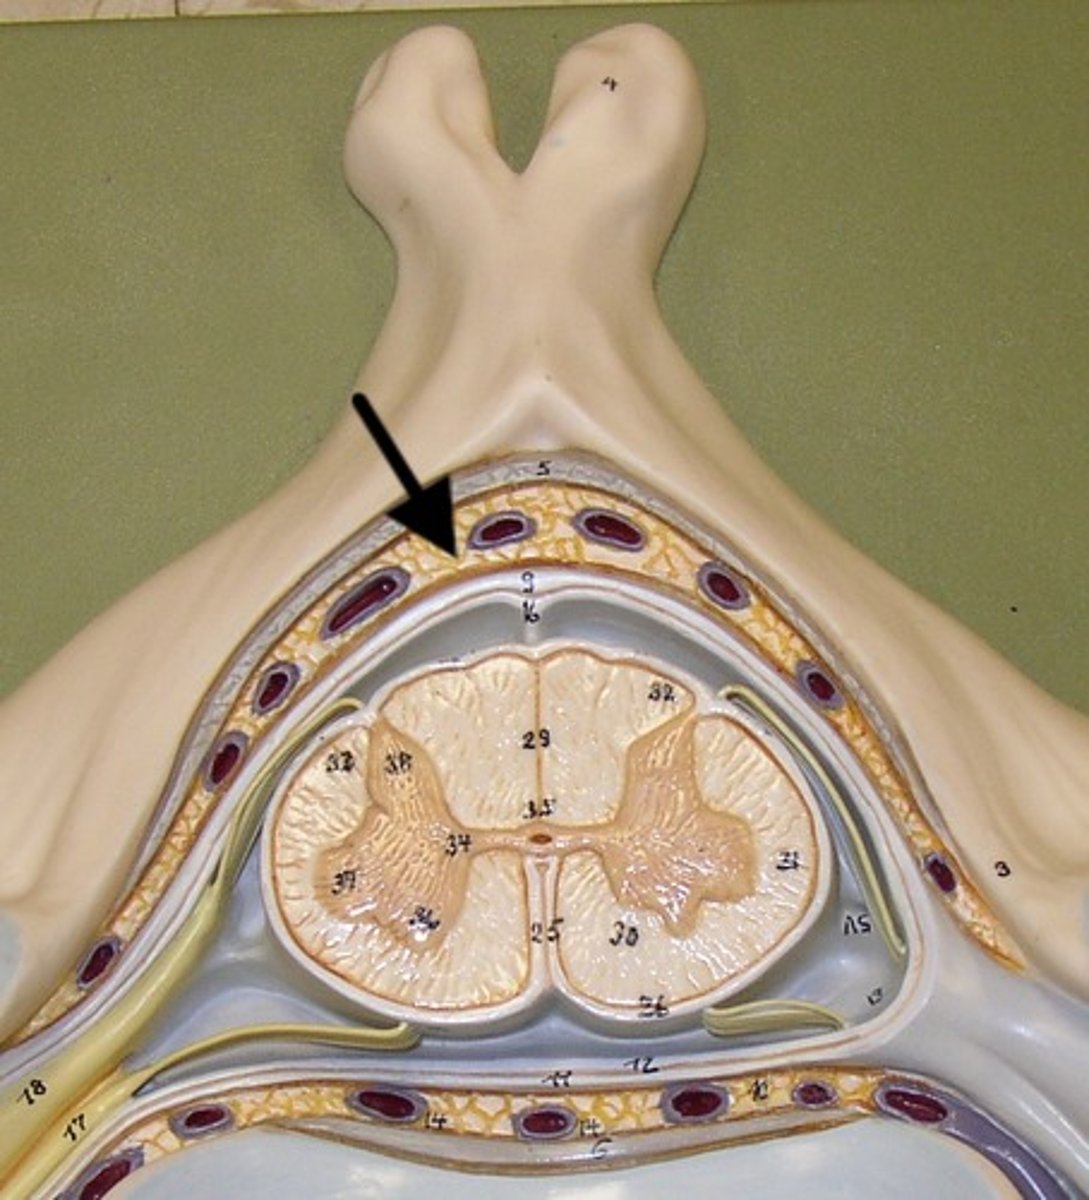

epidural space

dura mater

thick, outermost layer of the meninges surrounding and protecting the brain and spinal cord

subdural space

space between dura mater and arachnoid mater

arachnoid mater

middle layer of the meninges

B on model